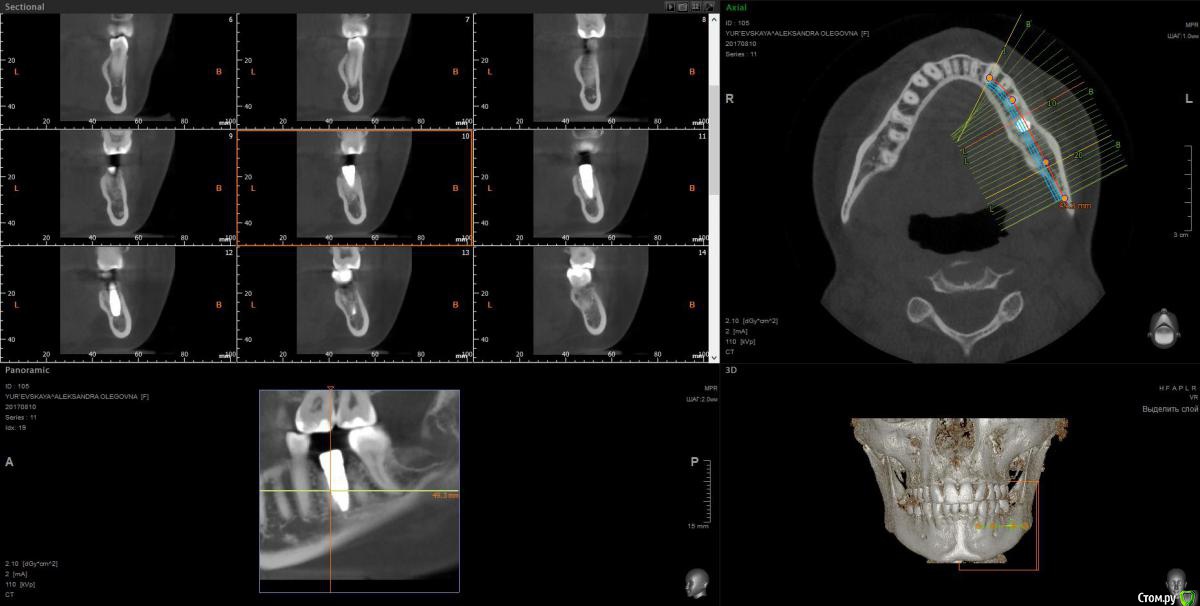

wladdX Опубликовано 28 сентября, 2017 Поделиться Опубликовано 28 сентября, 2017 Ссылка на комментарий

Павел7809 Опубликовано 28 сентября, 2017 Поделиться Опубликовано 28 сентября, 2017 (изменено) А восьмой зуб давно удаляли? Возможно это моя больная фантазия, но покрутив кт я увидел 2 канал нижнечелюстного. Посмотрел еще раз, он там точно есть Изменено 28 сентября, 2017 пользователем Павел7809 Ссылка на комментарий

Kobusha Опубликовано 28 сентября, 2017 Автор Поделиться Опубликовано 28 сентября, 2017 (изменено) А восьмой зуб давно удаляли? Возможно это моя больная фантазия, но покрутив кт я увидел 2 канал нижнечелюстного. Посмотрел еще раз, он там точно естьВосьмерку со стороны имплантата - в мае. Ретинированный зуб был. Нижнечелюстного нерва? а что это значит? =) наличие данного канала? Изменено 28 сентября, 2017 пользователем Kobusha Ссылка на комментарий

Kobusha Опубликовано 28 сентября, 2017 Автор Поделиться Опубликовано 28 сентября, 2017 (изменено) upd. по истории: сходила к имплантологу. Посмотрел кт еще раз(то, которое выше), сделал прицельный снимок. (отдавать или пересылать на почту отказались). ничего не видит. причину боли определить не может, посылает к терапевту. и хочет опять устанавливать временную коронку в ближайшее время(его рабочая версия, что в прошлый раз - коронка люфтила, давая болевой синдром). Но боль-то присутствует.Буду признательна за какие-либо альтернативные точки зрения. Изменено 28 сентября, 2017 пользователем Kobusha Ссылка на комментарий